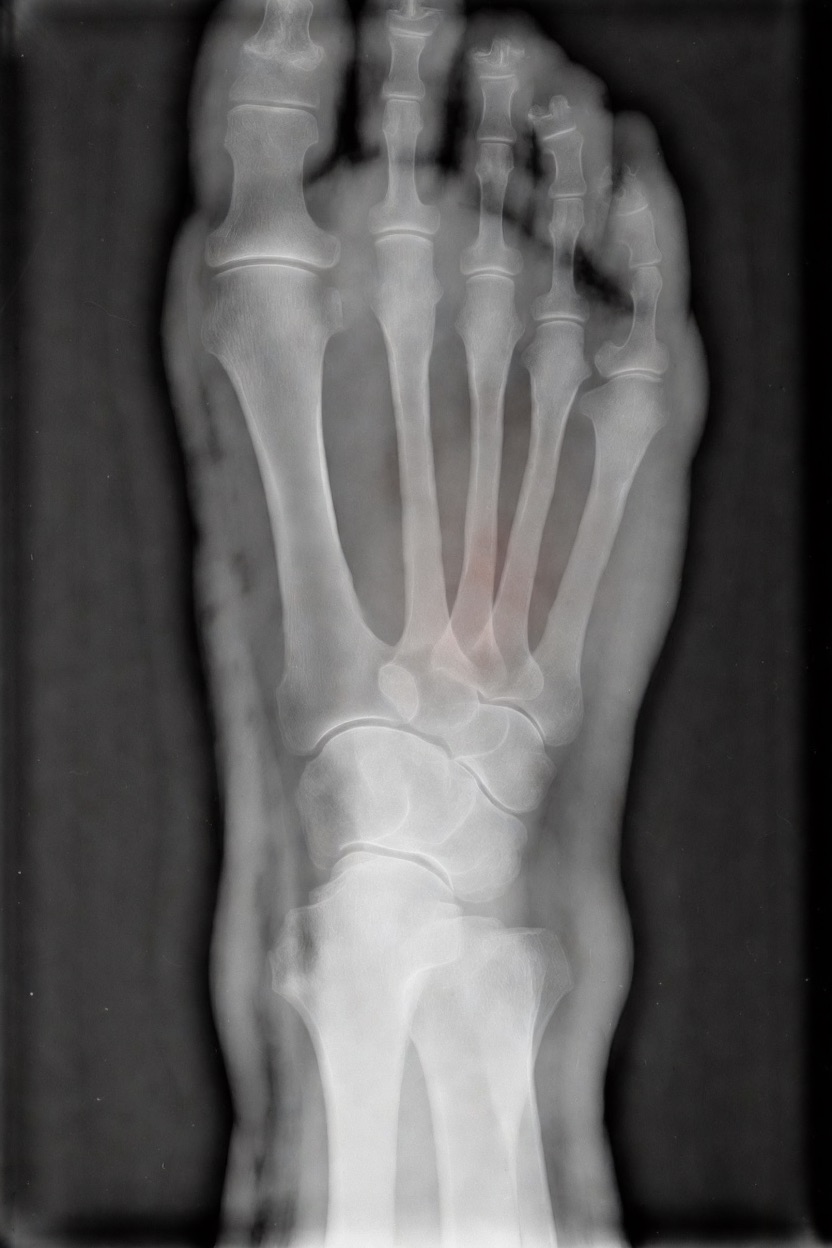

アートや写真の編集用に設計されたFlux Kontextのようなモデルを、医療画像、たとえば「単純な」骨折の赤色マーキングに使用できるか?

即答:面白い結果を出すが、過剰に反応し、医療ツールとしては信頼性に欠ける。これはアイデアを試すためのプロトタイプに過ぎない。

テスト結果:

- 偽陽性 ≈ 24%

- 骨折検出 ≈ 20%

感度モード(検出を優先、ノイズ多め)

- Euler、15ステップ、Karras

- Denoise:1.0

結果:

- 偽陽性 ≈ 80%

- 骨折検出 ≈ 86%

さらに攻撃的な設定(例:rk beta57、Denoise 1.0)では、**偽陽性100%、検出100%**という馬鹿げた結果に:すべてを赤で塗りつぶし、健常部もほぼすべて骨折と誤認する。未経験の目には区別がつかない。

Civitai用に作成した、100% AI生成の合成ミニデータセット(健康なX線10枚、骨折のあるX線10枚)でテスト:

- 健康な骨での偽陽性:100%

- 骨折検出:≈ 45%